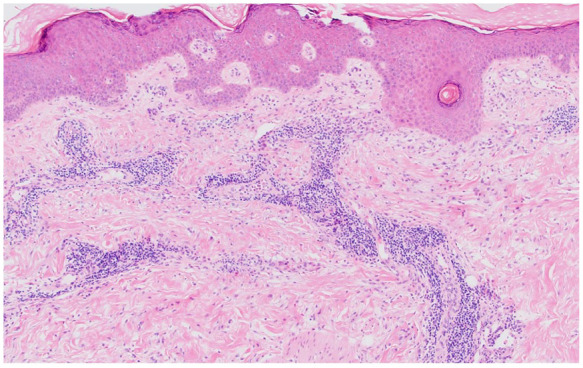

When there is concern that a rash may be a drug eruption reaction, there are many well-known culprits such as antibiotics and phenytoin. When an uncommon or previously unknown offending medication is being considered to have caused a drug eruption, diagnostic skin biopsy can help confirm the diagnosis. Our patient is a 54-year-old female with past medical history of prediabetes and obesity. She had ST segment-elevation myocardial infarction that was treated appropriately with timely percutaneous coronary intervention, which included angioplasty and drug-eluting stent placement. She was maintained on treatment regimen, and over the next 3 months, she developed a worsening maculopapular rash across her torso and upper extremities. Her biopsy showed superficial and mid-dermal perivascular lymphohistiocytic inflammation with focal spongiosis and scattered eosinophils, a common pathologic finding seen in drug eruptions. Although the patient was not taking any well-known offending agents, her ticagrelor was discontinued and she was transitioned to clopidogrel. Shortly after the transition, the patient's drug rash resolved without recurrence. Drug eruptions are a common etiology for rashes leading to presentation in primary care clinics. Our patient illustrates an exceedingly rare case of ticagrelor-induced drug reaction, as a review of the literature shows only 2 previously published case reports.